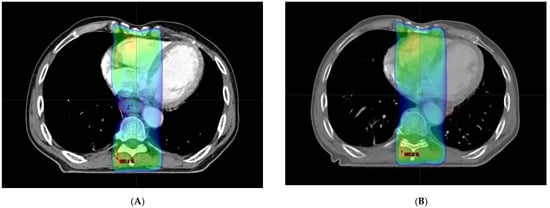

Definitive concurrent chemoradiation was scheduled. The radiation dose was 50.4 Gy/28 fractions over 5.5 weeks. The patient had received continuous infusion of 5-fluorouracil (1000 mg/m2) on days 1 through 4 and days 22 through 25 and cisplatin (75 mg/m2) was given on days 1 and 22. By 3 weeks after commencement of chemoradiation, the esophagus was outside of the radiotherapy field during image-guided radiotherapy. Follow-up CT revealed that the esophagus had moved from the right of the aorta to the left (Figure 2C,D). Fusion of the radiation plan and follow-up CT showed that prescription dose did not cover the entire esophagus (Figure 3).

Rumor regression throughout treatment would induce organ movement [1,2,3]. To achieve successful tumor regression, radiation therapy requires several weeks of radiation to be delivered accurately to the tumor [4]. Usually, a 5–10 mm margin is allowed for set-up error and internal organ motion. However, this case exhibited an unexpectedly large movement of the esophagus across the aorta with tumor regression that extended outside the margin and thus outside the radiotherapy field. Though organ movement with tumor regression is usually shown in the uterus, rectum and lung, little known of this in the esophagus [2,5]. These movements may affect subsequent invasive examinations or treatment during cancer therapy. In this case of unexpected large movement of the esophagus due to tumor regression, we revised the radiotherapy plan to reflect the new esophageal position. This implied that regular imaging and close monitoring are required during the treatment of esophageal cancer, especially for large esophageal lesions. Metal markers or clips would be helpful in monitoring the movement of the esophagus because they can be localized on a plain radiograph.

Figure 3. (A) Initial radiation plan. Esophagus (red line) is covered with 95% of prescription dose. (colored area). (B) Radiation plan with moved esophagus (red line). Part of esophagus was outside radiation field.